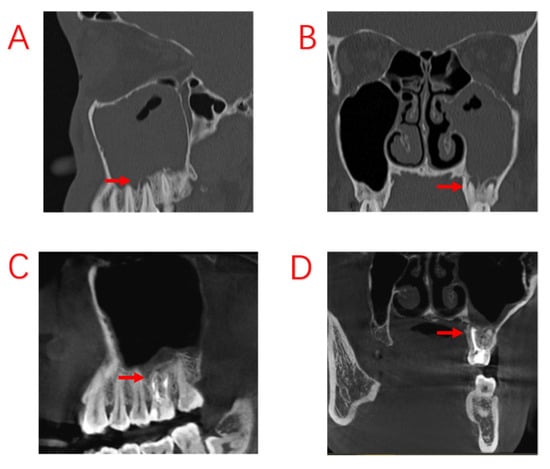

In this study, we compared the EPL, AP, and PE groups in terms of demographic characteristics, sinus symptoms, and extent of sinus invasion. The three groups were found to have statistically significant differences in terms of sex and age, with patients in the PE group being older. There were no statistically significant differences in sinusitis symptoms among ODS patients with different odontogenic etiologies. However, the proper treatment of odontogenic lesions can affect the overall outcome for the patient, and different treatments are required for different odontogenic causes. In a recently published consensus, experts in the survey agreed that a multidisciplinary approach was optimal []. We also believe that multidisciplinary collaboration is essential and have proposed different treatment approaches for different etiologies. Patients with ODS caused by AP tended to have a better prognosis, excluding those who had already had root canal treatment (RCT), root fractures, and periodontal lesions. For those patients whose lesions were limited to the apices of the teeth, infection from the pulp could be blocked by RCT, potentially avoiding the ESS procedure. Therefore, it is recommended that patients with ODS caused by periapical lesions undergo dental treatment first. The infection from the pulp was controlled with RCT, and the patients’ sinus symptoms subsequently improved as early as during the RCT procedure (Figure 2). After RCT, the decision to perform ESS was based on sinusitis symptoms and radiological findings. If the lesions are more extensive, involving root bifurcation, root fracture, or periodontal inflammation, extraction of the diseased tooth should be considered to completely remove the lesion (Figure 3). In some of our cases, the diseased teeth were extracted before the ESS procedure, but the sinusitis symptoms did not improve even after the mucosa in the oral cavity had healed. Although the pathological irritation from the oral cavity was resolved, the obstruction of the sinus openings resulted in the formation of an anaerobic environment in the maxillary sinuses, requiring the ESS procedure to improve sinus ventilation and drainage (Figure 4).

Figure 2.

Odontogenic sinusitis due to periapical inflammation. Symptoms disappeared after root canal treatment; no ESS was performed. (A,B): Before root canal treatment, the patient developed a purulent discharge with a foul odor and obstruction of the maxillary sinus opening. (C,D): After root canal treatment, infection of the dental pulp was controlled and the symptoms of sinusitis had disappeared, with the mucosa of the maxillary sinus returning to normal. Red arrows indicate sites of apical inflammation.